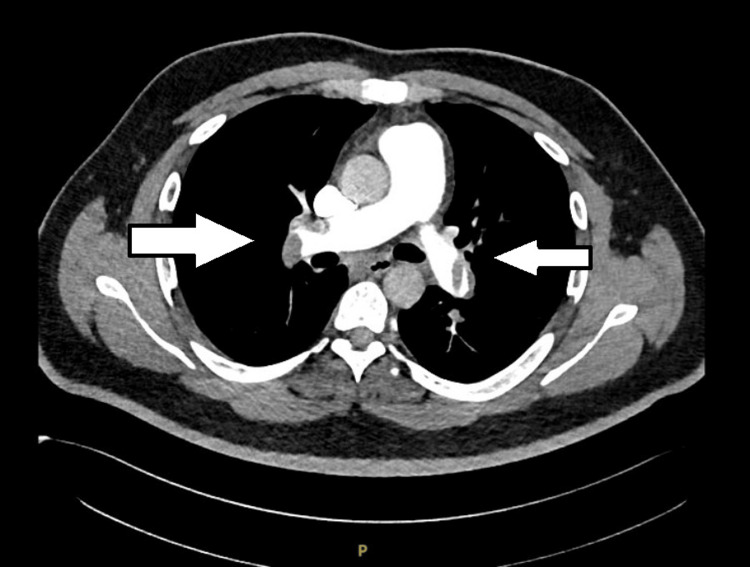

The real-time reverse transcription-polymerase chain reaction (RT-PCR) for COVID-19 was negative. The CT pulmonary angiography revealed multiple filling defects in superior and inferior segmental branches of both pulmonary arteries suggestive of pulmonary thromboembolism (Figures 2–3).